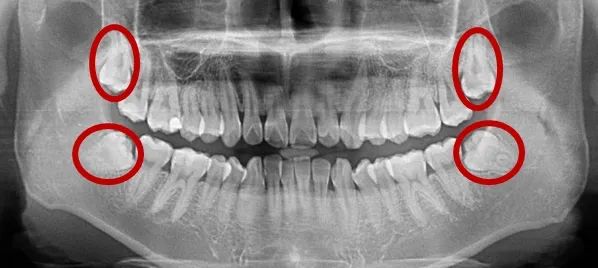

而智齿长出来最晚,先长出来的哥哥姐姐们,先到先得,把本来就位置不富裕的上下颌骨占得差不多了,这就导致最小的智齿兄弟没有足够的容身之所,故经常东倒西歪,倒着挤着前面的大牙,成为了“阻生智齿”。

还有一些倒着的智齿,顶着前面的大牙,不仅长期塞牙,滋生细菌,甚至还把前面的大牙顶坏,导致前面的大牙也无法保留。